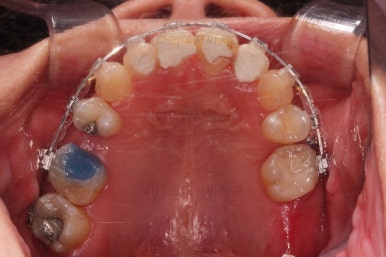

마무리 못한 어금니 치료와 앞니 심미보철을 마무리 합니다.

앞니 심미보철까지 마무리 되었습니다.

물론 윗니 맨 뒤쪽 치아 한 군데는 임플란트가 들어가는 것이 가장 좋은데요.

이 부분은 여러 가지 사정들을 생각해서 좀 더 고민해 보시기로 했습니다.

중간 치아가 비어있다면 인접한 치아들이 쓰러진다거나 문제가 생길 수 있는데 맨 뒤 치아가 비어있다면 그것보다는 문제가 심각하진 않습니다.